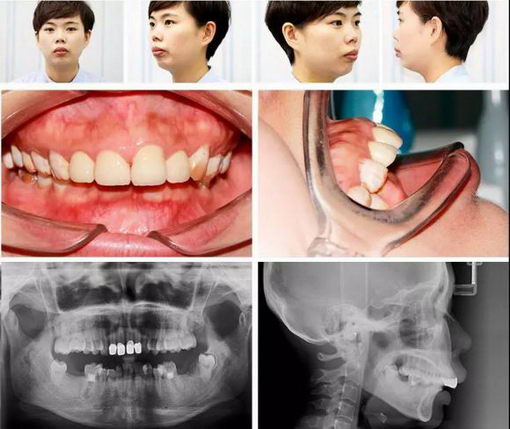

真实案例分享:半隐型(陶瓷)自锁托槽矫正

真实案例分享:隐型矫正